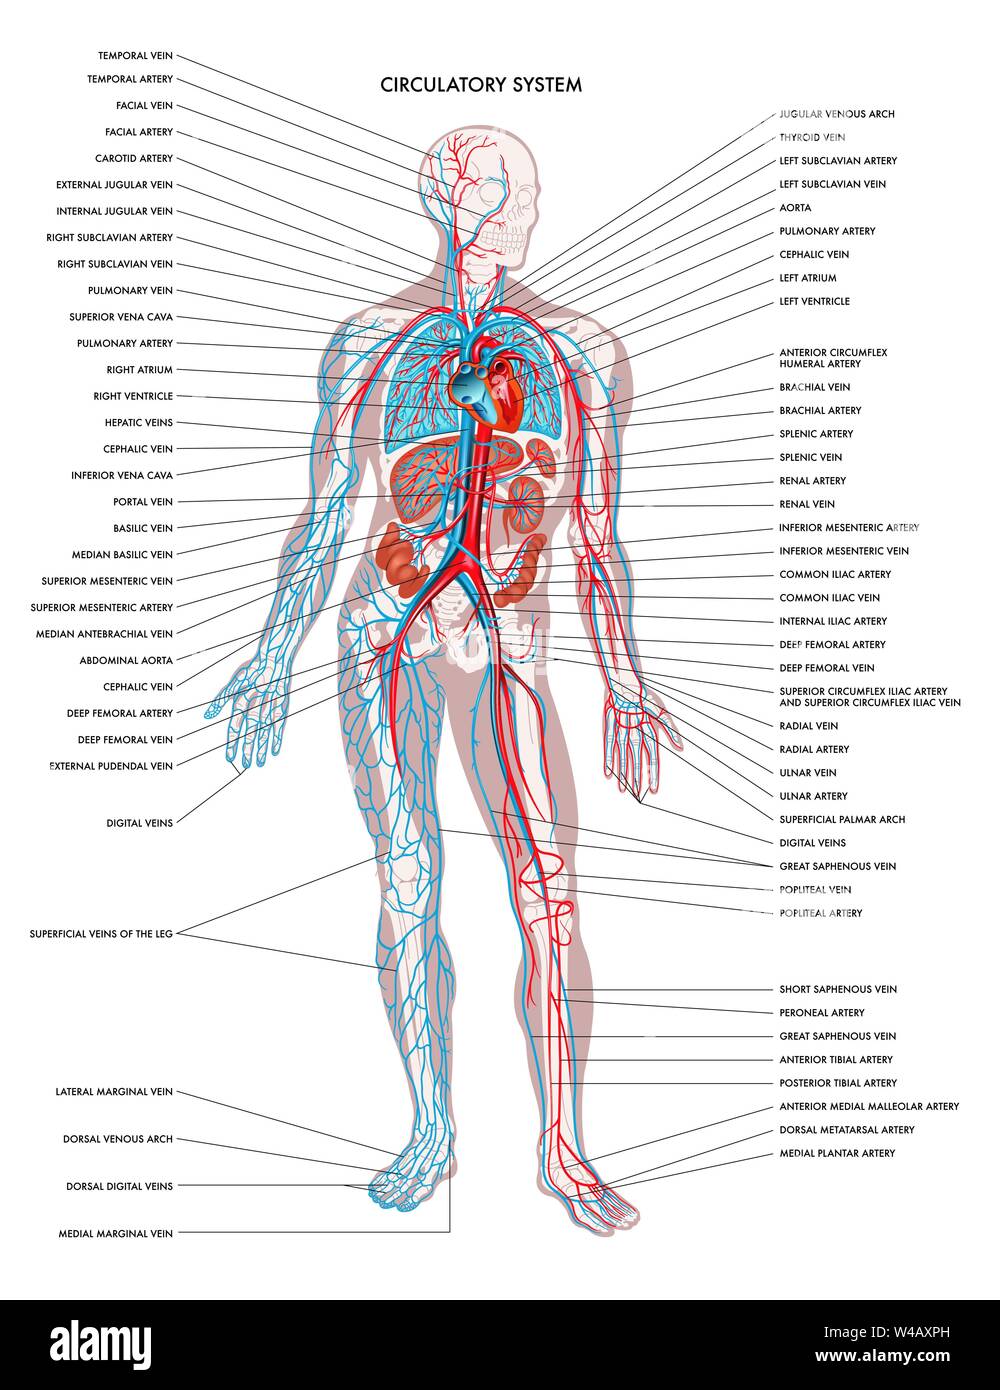

Labelled diagram showing the details of the human body circulatory system. Stock Photohttps://www.alamy.com/image-license-details/?v=1https://www.alamy.com/labelled-diagram-showing-the-details-of-the-human-body-circulatory-system-image336316899.html

Labelled diagram showing the details of the human body circulatory system. Stock Photohttps://www.alamy.com/image-license-details/?v=1https://www.alamy.com/labelled-diagram-showing-the-details-of-the-human-body-circulatory-system-image336316899.htmlRF2AF4FHR–Labelled diagram showing the details of the human body circulatory system.

Labelled diagram showing the details of the human body circulatory system. Stock Vectorhttps://www.alamy.com/image-license-details/?v=1https://www.alamy.com/labelled-diagram-showing-the-details-of-the-human-body-circulatory-system-image260854681.html

Labelled diagram showing the details of the human body circulatory system. Stock Vectorhttps://www.alamy.com/image-license-details/?v=1https://www.alamy.com/labelled-diagram-showing-the-details-of-the-human-body-circulatory-system-image260854681.htmlRFW4AXPH–Labelled diagram showing the details of the human body circulatory system.